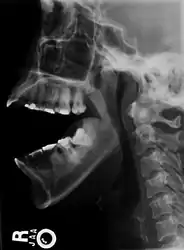

There are four different positions of jaw dislocation: posterior, anterior, superior and lateral. The most common position is anterior, while the other types are rare. Anterior dislocation shifts the lower jaw forward if the mouth excessively opens. This type of dislocation may happen bilaterally or unilaterally after yawning. The muscles that are affected during anterior jaw dislocation are the masseter and temporalis which pull up on the mandible and the lateral pterygoid which relaxes the mandibular condyle. The condyle can get locked in front of the articular eminence. Posterior dislocation is possible for people who get injured by being punched in the chin. This dislocation will push the jaw back affecting the alignment of the mandibular condyle and mastoid. The external auditory canal may be fractured. Superior dislocations occur after being punched below the mandibular ramus as the mouth remains half-open. Since great force occurs in a punch, the angle of the jaw will be forced upward moving towards the condylar head. This can result in a fracture of the glenoid fossa and displacement of the condyle into the middle cranial fossa, potentially injuring the facial and vestibulocochlear nerves and the temporal lobe. Lateral dislocations move the mandibular condyle away from the skull and are likely to happen together with jaw fractures.[4][5]

Posterior, superior and lateral dislocations are uncommon injuries and usually result from high-energy trauma to the chin. By contrast, anterior dislocations are more often the result of low-energy trauma (e.g. tooth extraction) or secondary to a medical condition that affects the stability of the joint (e.g. seizures, ligamentous laxity, degeneration of joint capsule).

-

Side view of the skull with anterior dislocation of jaw. -

Side view of the skull with posterior dislocation of jaw. -

Side view of the skull with superior dislocation of jaw. -

Front view of the skull with lateral dislocation of jaw.